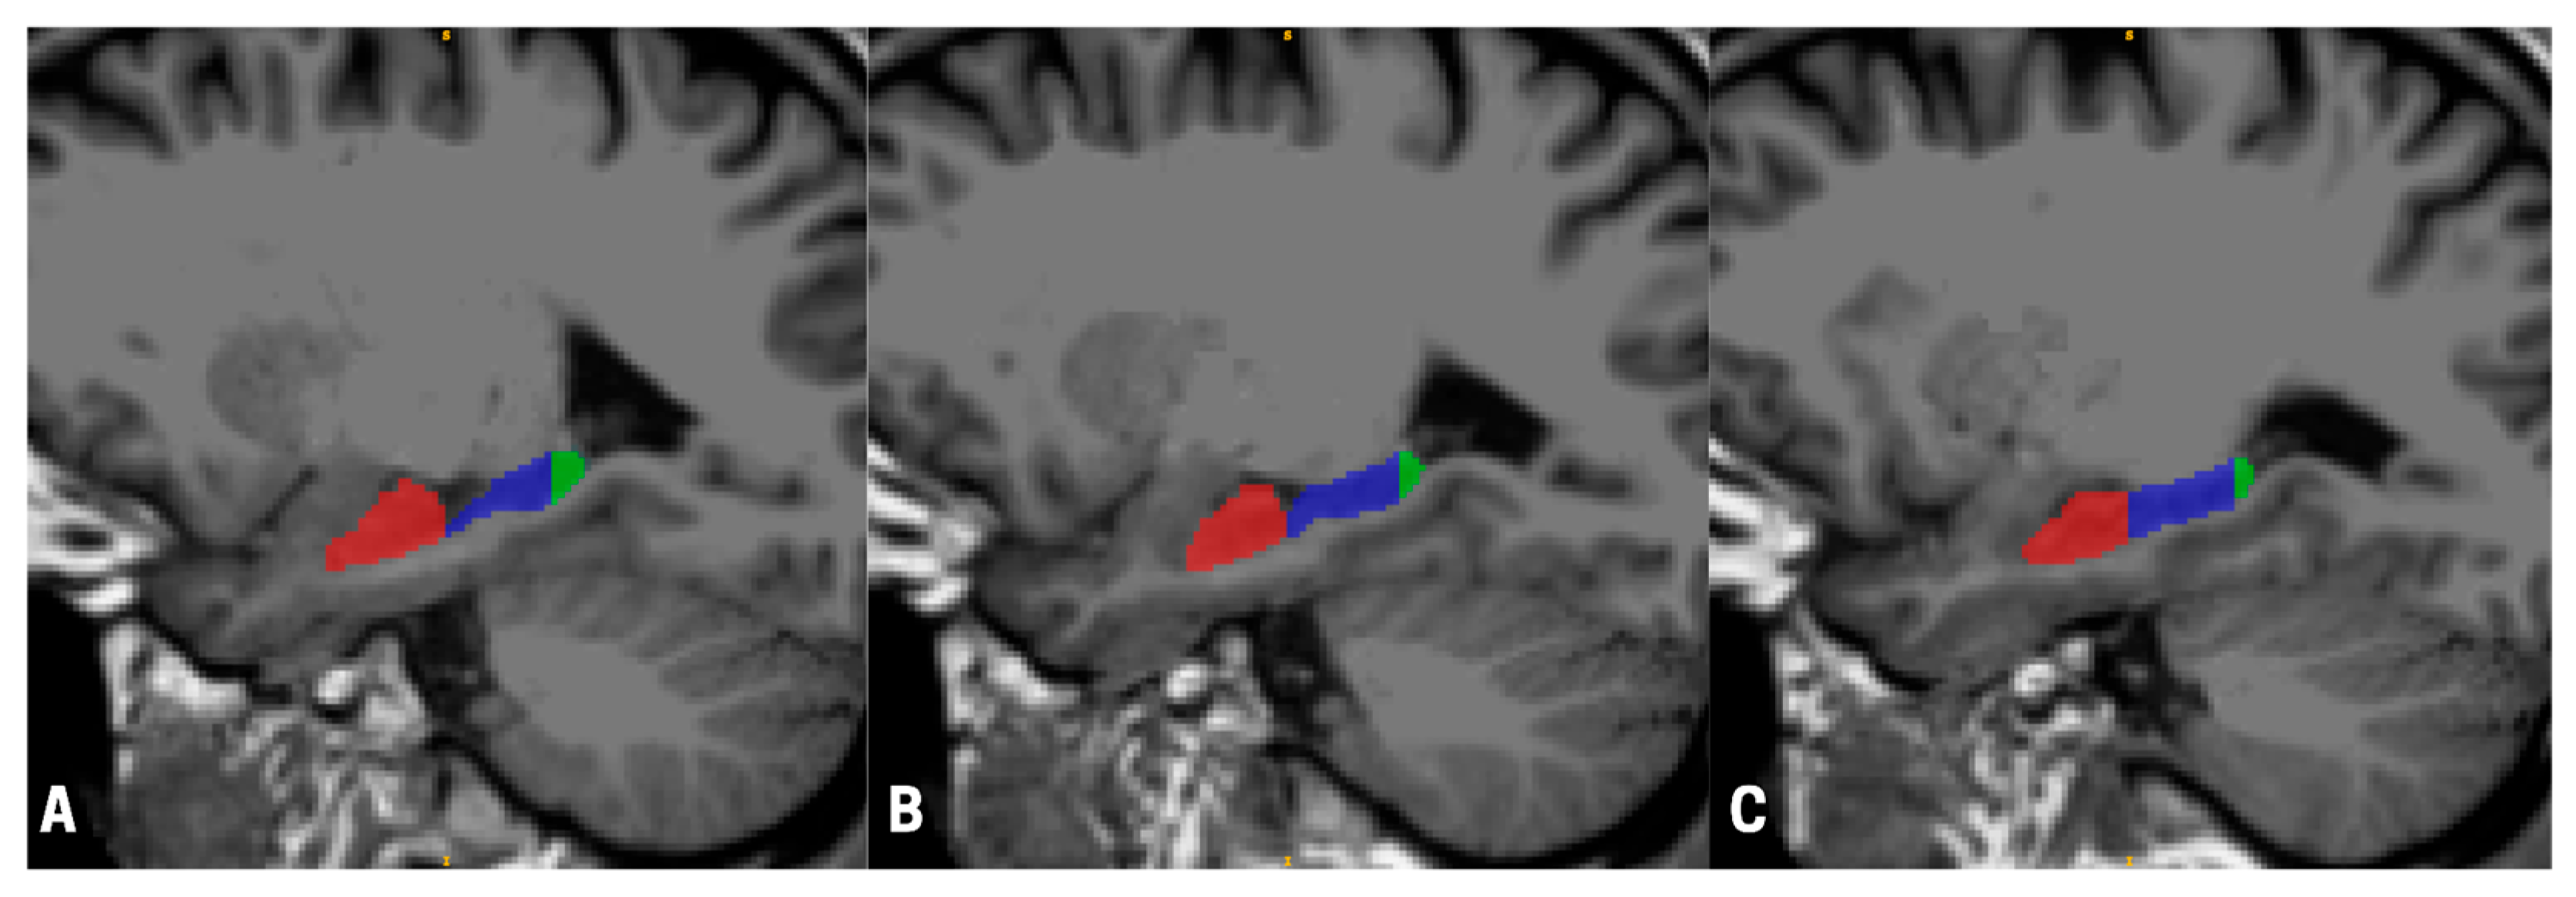

Figure 1.

Sagittal views of a T1-weighted magnetic resonance imaging (MRI) scan illustrating hippocampal subregional segmentation across three medial-to-lateral slices (A–C). The anterior hippocampus is shown in red, the body in blue, and the posterior hippocampus in green. Segmentation was performed automatically using FreeSurfer and manually quality-checked in accordance with the Harmonized Hippocampal Protocol [29] to ensure anatomical accuracy. Visualizations were rendered using ITK-SNAP (version 0.19.2), with panels progressing laterally toward the outer edge of the skull (A–C).